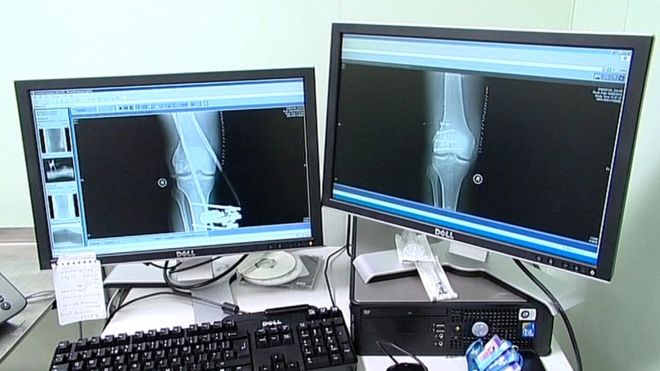

The role of the radiologist is vital in cancer diagnosis.

A medical doctor, they specialise in diagnosing and treating disease and injury through the use of medical imaging technology such as X-rays.